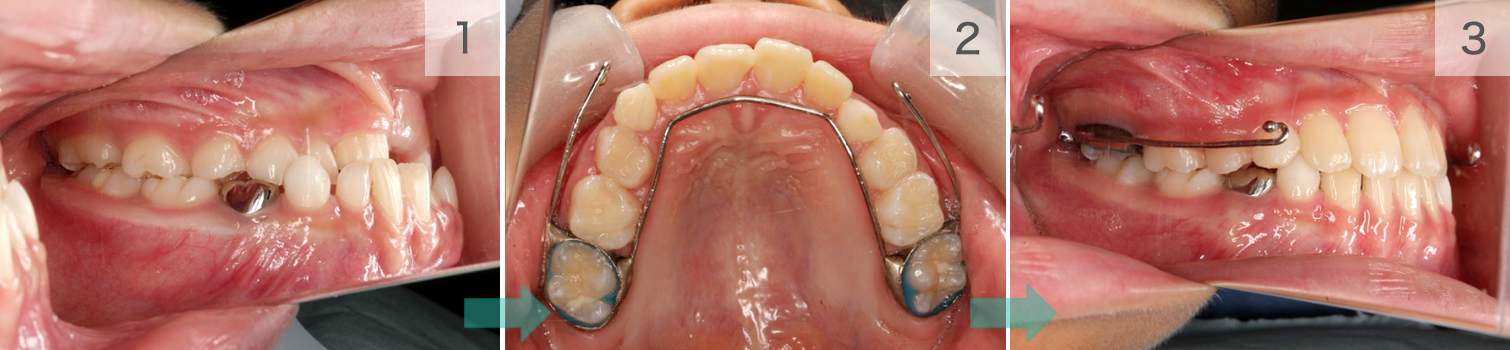

症例07. リンガルアーチ

舌側の主線とバンドで構成されます。

歯列の幅を維持したり、土台にして歯を引っ張ったり、押したりと活躍の場は多いです。

| 治療内容 | 1:最後臼歯が外側に張り出している 2:リンガルアーチ後方のアームから歯を引く 3:歯が内側に移動する |

|---|---|

| 期間 | 半年~1年 |

| 費用 | 300,000円+税 |

| リスク | 磨きづらい箇所は虫歯になるリスクが あります。 |